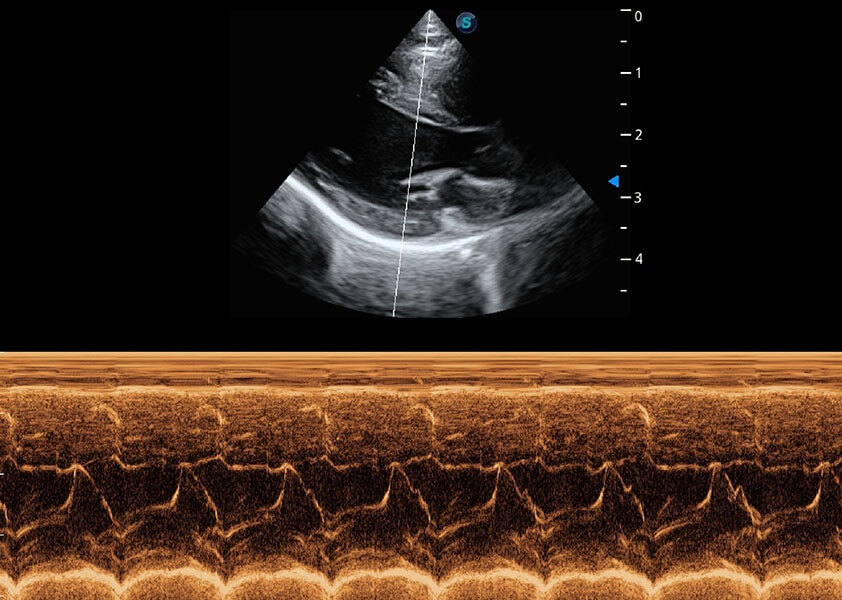

优异的基础图像

(犬)乳头肌短轴

(猫)二尖瓣M型

• AMM 解剖M型

通过360度任意调节3条M型取样线,在同一心动周期上观察心脏不同位置的运动曲线,得到准确的心功能测量数据,有效评估心肌运动及左心室功能。